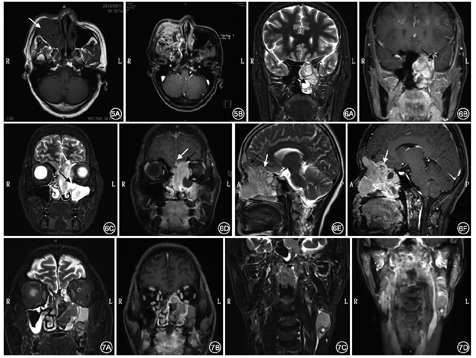

鼻咽纤维血管瘤好发于青少年男性,CT检查可提供术中所需的解剖标志,但MRI对判断肿瘤的范围、边界、侵犯翼腭窝、颞下窝、眶下裂、翼管和圆孔的程度、肿瘤血供情况有重要作用,特别对于复发的病例。若肿瘤与周围软组织粘连,MRI更有助于分辨病变与正常组织。原发的鼻咽纤维血管瘤在增强MRI中表现为起源于蝶腭孔或翼管的不均质肿块,T1WI、T2WI混杂信号,肿块内见多量流空血管影,增强后呈均匀显著强化[8]。肿瘤可向外侧突入翼腭窝、颞下窝和眶下裂,向上方突入蝶窦、筛窦、圆孔和海绵窦,向下方自后鼻孔突入鼻咽腔,向后方突向翼管、翼突根部和翼内外板之间,到达颈内动脉前方和破裂孔。MRA及CE-MRA可判断肿瘤血供情况,大部分的鼻咽纤维血管瘤血供来自于颌内动脉和咽升动脉,若肿瘤突向上生长则可能由颈内动脉及颈外动脉的分支共同供血,也可能由对侧的颈内和颈外动脉供血。在这种情况下,增强MRA对判断是否需行术前DSA栓塞、如何栓塞、手术风险、手术难度有很大帮助。

鳞状细胞癌和腺癌好发于中老年患者,大部分起源于上颌窦,其次为鼻腔、筛窦,软组织肿物伴骨质破坏是其CT特征表现[8],但CT能够提供的信息非常有限,MRI平扫+增强是常规的检查方法。这两种肿瘤在MRI上表现为T1WI等或稍低信号,T2WI等或稍高信号,增强呈不均匀强化,提示局部可能有坏死、出血(图5)。大部分鳞状细胞癌和腺癌破坏周边骨质,T1增强抑脂序列对判断眶内、颅底侵犯,以及神经、肌肉侵犯有重要作用。当肿瘤侵犯骨质时,T1WI上骨髓高信号被肿瘤取代表现为低信号。若肿瘤突破硬脑膜及蛛网膜,在T2WI上表现为脑组织周围高信号的脑脊液被等信号软组织肿瘤侵犯。腺癌的MRI信号取决于黏液含量、是否伴瘤内出血和细胞结构,黏液含量高的腺癌表现为T2WI高信号,黏液含量低的腺癌表现为T2WI等、稍高信号。

腺样囊性癌是一类生长缓慢的涎腺来源恶性肿瘤,常见于50~60岁患者,上颌窦是其好发部位,其次是鼻腔、筛窦和蝶窦。其组织学上可分为小梁型、筛孔型和硬化型,呈局部浸润生长,具有嗜神经性,容易局部复发和远处转移,可分为膨胀性生长型伴低度骨质缺损和破坏型伴广泛骨质破坏。腺样囊性癌在MRI上表现为T1WI等信号,T2WI等、稍高信号,沿神经生长,常累及三叉神经上、下颌支[10]、海绵窦甚至颅内[11]。

嗅神经母细胞瘤是起源于嗅上皮(神经内胚层)的恶性肿瘤,常见肿瘤中心位于筛板、上鼻甲和鼻中隔上1/3。嗅神经母细胞瘤发病年龄范围广,但具有20岁和60岁两个高峰[12]。嗅神经母细胞瘤常直接侵犯鼻窦、筛板、颅底和眶,疾病进程中常出现颈部淋巴结转移(20%~25%)和远处转移(10%~40%)。MRI上表现为T1WI较灰质信号低、T2WI较灰质信号高的肿块[13],增强后除坏死和出血外呈均匀强化(图6)。

恶性黑色素瘤是来源于色素细胞的恶性肿瘤,在黏膜恶性黑色素瘤中,鼻腔鼻窦为第二好发部位。侵犯黏膜的恶性黑色素瘤恶性程度高,根据美国癌症联合委员会(AJCC)分期,未侵犯骨质的为T3肿瘤。恶性黑色素瘤可分为黑色素型和无色素型,色素含量在某种程度上决定其在MRI中的表现,典型的黑色素型肿瘤T1WI呈高信号,T2WI呈等、低信号,而无色素型表现为T1WI低信号、T2WI高信号,增强MRI呈轻到中度强化(图7)[14]。